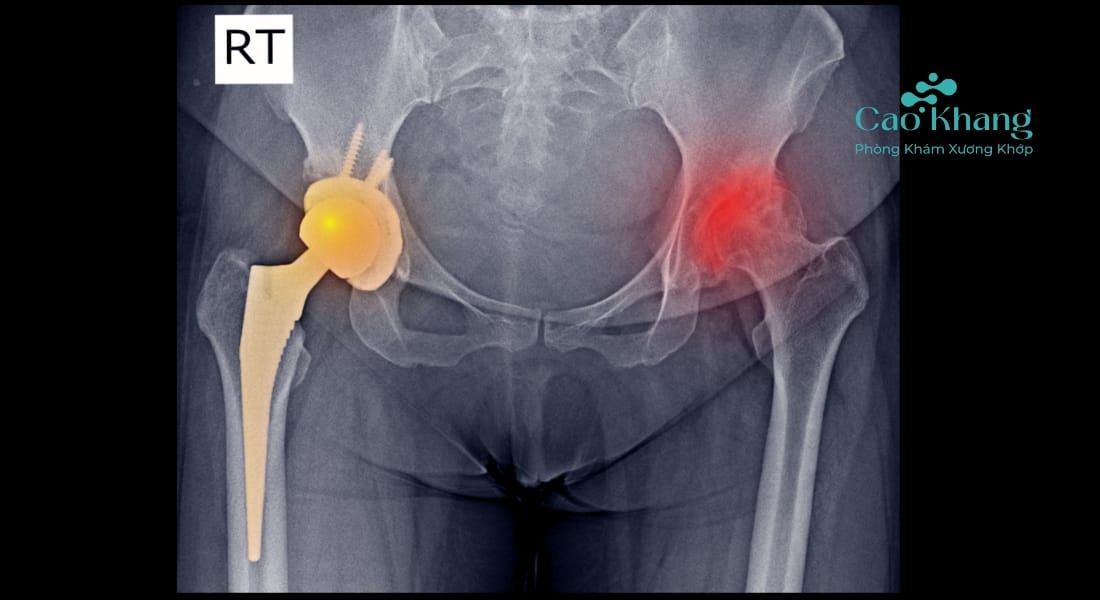

1. Trật khớp háng kiểu chậu (trật ra sau)

Chiếm tới hơn 90% ca trật khớp háng. Thường gặp khi đầu gối bị đập vào vật cứng trong tư thế co gập (ví dụ tai nạn xe máy). Chân bị trật thường xoay vào trong, đầu gối co lên, chân ngắn lại.

- Khám lâm sàng: Quan sát biến dạng chi, đánh giá đau, phản xạ thần kinh.

- X-quang: Để xác định hướng trật, có mảnh xương gãy kèm theo không.

a. Nắn trật khớp háng kín

Là phương pháp phổ biến và ít xâm lấn nhất. Bác sĩ sẽ gây mê toàn thân và sử dụng kỹ thuật chuyên môn để đưa chỏm xương đùi trở lại ổ cối. Sau khi nắn trật khớp háng, bệnh nhân cần nằm bất động và theo dõi chặt chẽ biến chứng.